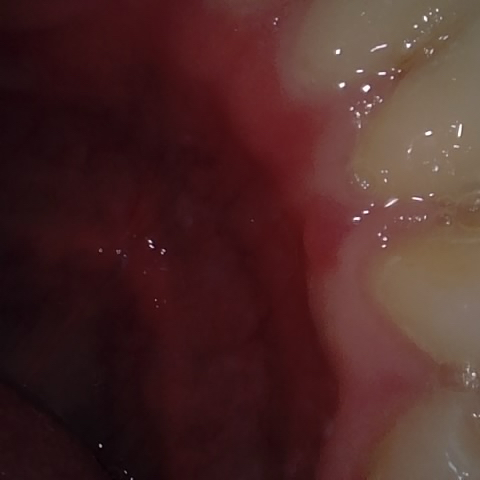

Annotated as "Bad"